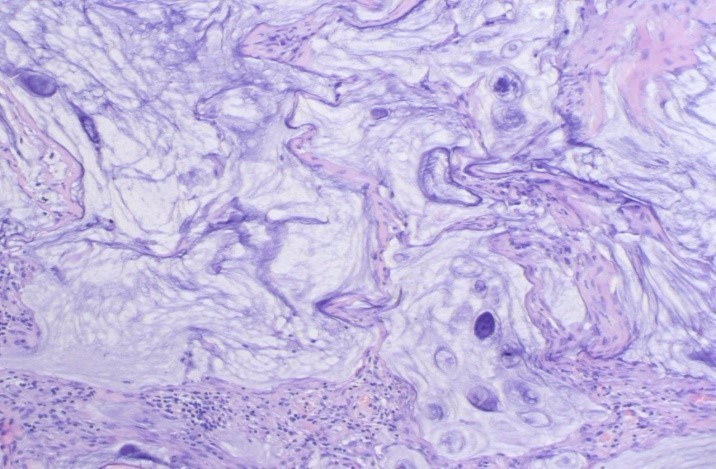

腹腔镜下观察:肝脏、脾脏、全部结肠和系膜、腹主动脉旁、乙状结肠系膜根部、盆腔侧壁无肿大淋巴结。可见大网膜形态异常,挛缩呈饼状,表面大量清亮滤泡,小肠轻度充血,肠间隙见大量纤维性渗出。经脐下纵行切口抬起大网膜,弯钳阻断大网膜组织内血管,切取约3 cm×3 cm大小网膜组织送检。病理诊断结果:(大网膜结节)大网膜弥漫黏液湖样结节,局灶见黏液上皮及异性黏液细胞,形态倾向浸润性或转移性黏液性肿瘤,免疫组化:villin(-)AE1/3(+)。

送上级医院会诊后回报:(大网膜结节)纤维脂肪组织中见大量黏液湖并见少量轻度异性的黏液性腺体,考虑为低级别腹膜假黏液瘤,请检查阑尾(见图4)。

图4大网膜弥漫粘液湖样结节,局灶见粘液上皮及异型粘液细胞